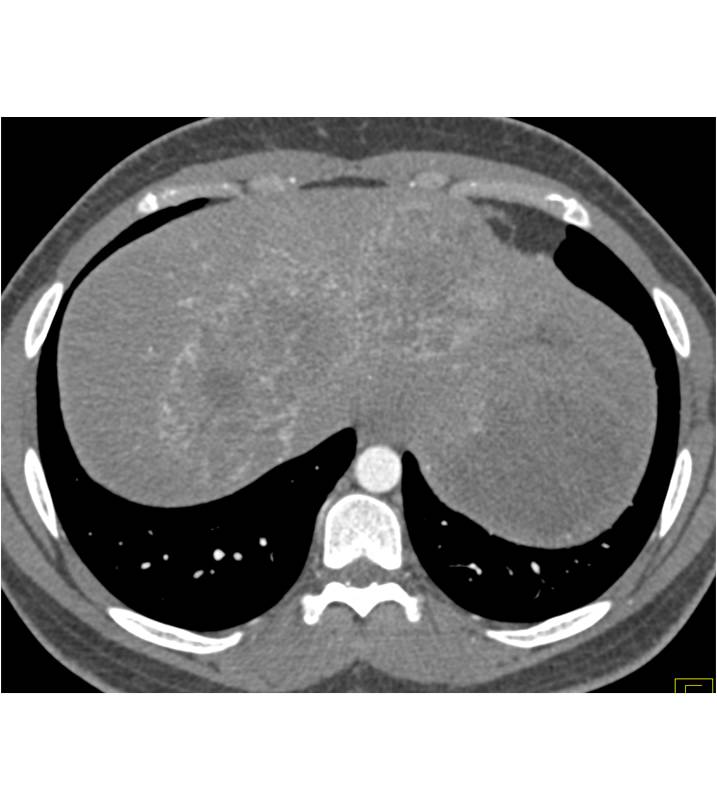

Splenic Granulomatous Disease